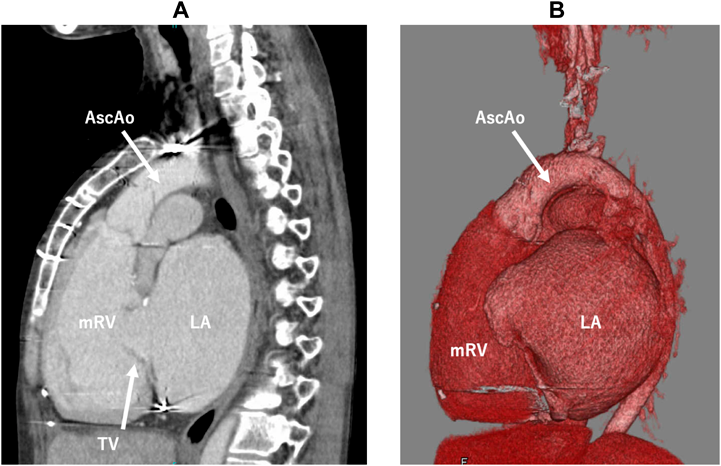

Her cardiac anatomy featured mesocardiac position, the systemic RV longitudinally elongated, and a short sagittal distance between the tricuspid valve and the apex of the systemic RV due to a severely dilated left atrium. The aorta was left anterior to the pulmonary trunk (Fig. 1). Therefore, standard VAD placement from the cardiac apex would cause troublesome sternal closure interfered by the pump body, inflow cannula obstruction due to close proximity to the tricuspid valve, and difficult anastomosis to the short anterior ascending aorta. In contrast, vertical VAD placement from the diaphragmatic surface towards the aortic valve seemed less hazardous resolving these challenges.

Fig. 1 Preoperative images on contrast enhanced computed tomography (A) and 3D computed tomography (B) showed the morphologically right ventricle longitudinally elongated, the left atrium markedly dilated, and the ascending aorta proportionally short.

AscAo, ascending aorta; LA, left atrium; mRV, morphologically right ventricle; TV, tricuspid valve.